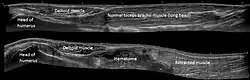

Panoramic ultrasonography of a proximal biceps tendon rupture. Top image shows the contralateral normal side, and lower image shows a retracted muscle, with a hematoma filling out the proximal space.

Tears of the biceps brachii may occur during athletic activities, however avulsion injuries of the distal biceps tendon are frequently occupational in nature and sustained during forceful, eccentric contraction of the biceps muscle while lifting.[20]